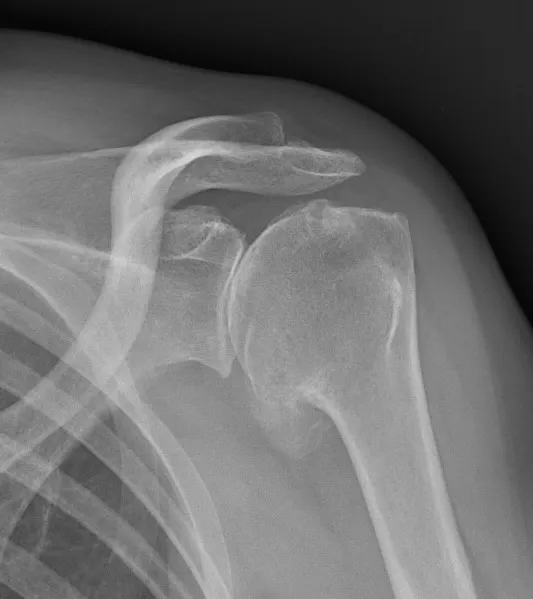

Aspect radiographique d'une omarthrose primitive